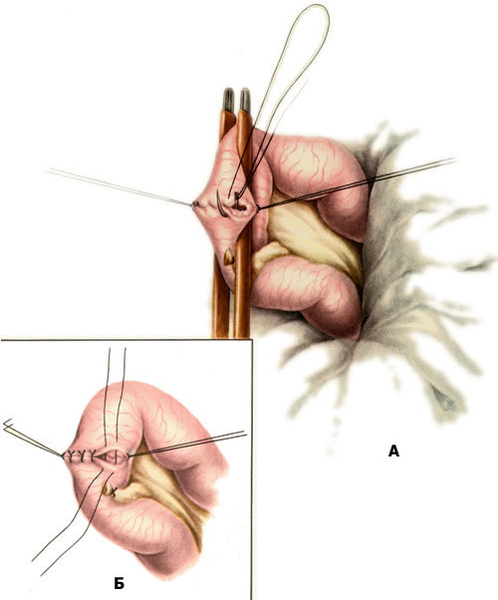

| 4. ЛЕЧЕНИЕ Бессимптомные дивертикулы удалять не следует. Дивертикул Меккеля подлежит удалению при дивертикулитах, язвах дивертикула, кишечной непроходимости, вызванной дивертикулом, свищах пупка, а также, по мнению ряда специалистов, при случайном обнаружении его во время операции. Производится резекция дивертикула с ушиванием стенки кишки (resectio diverticuli Meckelii). Техника операции. После вскрытия брюшной полости извлекают подвздошную кишку вместе с дивертикулом. Если диаметр дивертикула небольшой, то техника удаления его ничем не отличается от обычной аппендэктомии. В тех случаях, когда дивертикул широкий и имеет брыжейку, последнюю перевязывают и пересекают, освобождая основание дивертикула. Затем на кишку накладывают мягкий кишечный жом и производят отсечение дивертикула у его основания (рис. 3). Рану кишки ушивают в поперечном направлении к ее оси двухрядным швом (рис. 4). Брюшную полость зашивают наглухо. Рис. 3. Резекция дивертикула Меккеля. Отсечение дивертикула. Рис. 4. Резекция дивертикула Меккеля. Ушивание дефекта в стенке кишки двухрядным швом: а — наложение скорняжного шва; б — наложение узловых серозно-мышечных швов. Прогноз благоприятный. 5. ЛАПАРОСКОПИЧЕСКИЕ МЕТОДЫ В ДИАГНОСТИКЕ И ЛЕЧЕНИИ ДИВЕРТИКУЛА МЕККЕЛЯ |